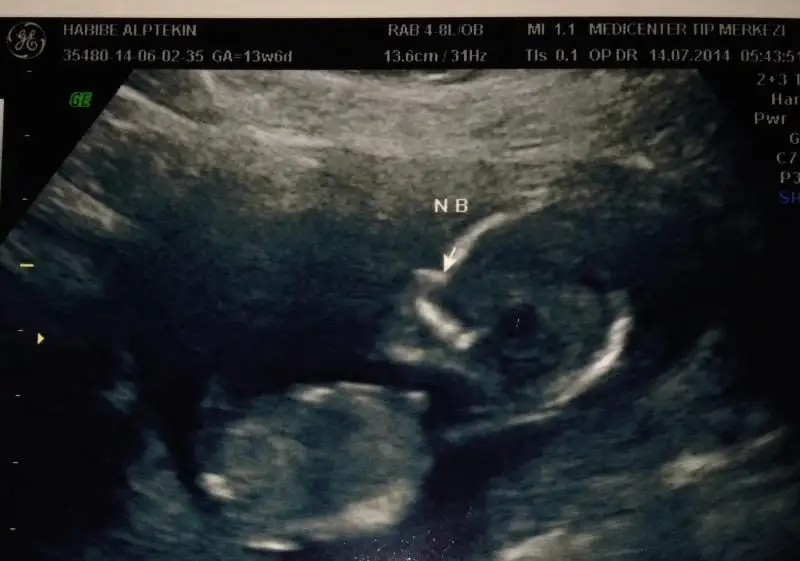

dr soylemeden siz gorun genital nub teorisi ( bebegin cinsiyeti)

Kizlar benim bebegim sizce nedir hic bi bilgim yok ..Orkdm sesisimi duyyorsan lutfen cevap yaz nasil ata bilirim resmi arkadaslar cep telefonundan yaa